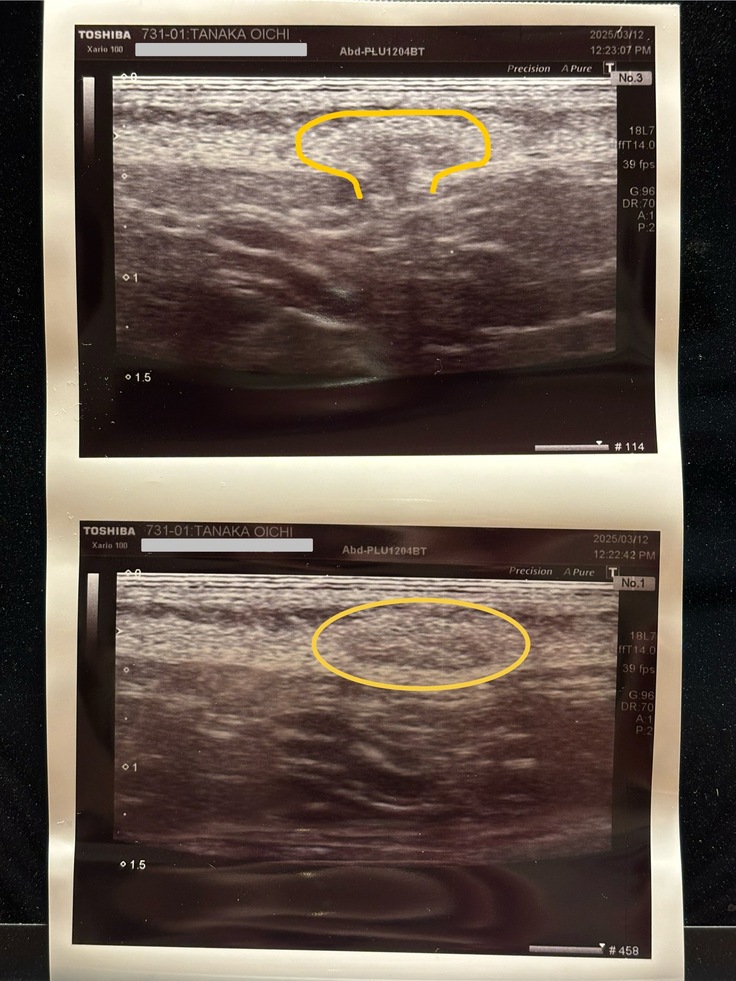

エコーをあてて診断の結果

【ヘルニア】であることが分かりました。

お市の場合、お腹の部分のヘルニアのため【臍ヘルニア】とのことです。

幸い出てきているものは脂肪だったため、急を要する状態ではありませんでしたが

放置していると、腸が出てきてしまい腸閉塞になる可能性もある様なので

今後、避妊手術の際に同時にヘルニアの穴を塞ぐのが得策とのことでした。

↓エコー検査結果

丸の部分は、厚さ2mm・幅7.2mmあるそうです。